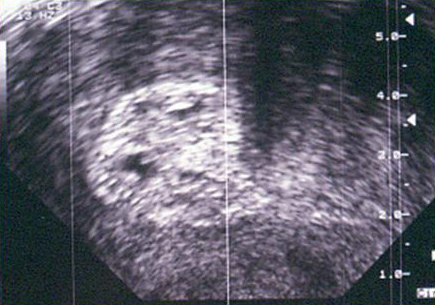

Endomètre type Tamoxifène